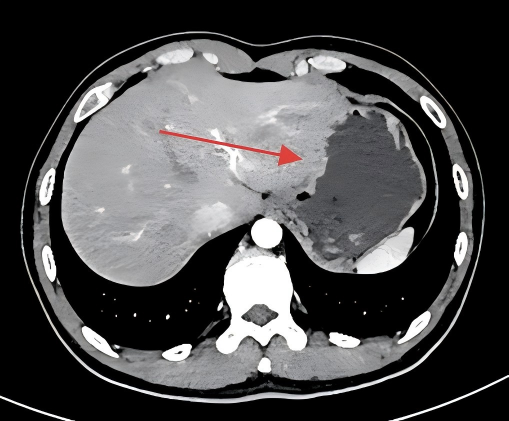

左起:图1a图1b

图1a检查时患者未喝水,胃壁显示的比较厚(红色箭头),此时若患者存在粘膜病变(如小溃疡或早期胃癌),很容易被漏掉。